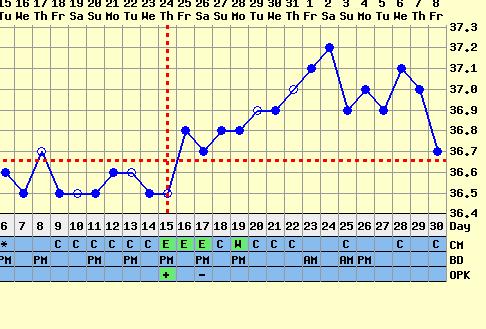

Megértelek a hőmérőzéssel kapcsolatban, azt hiszem, a helyedben én is mellőzném a nyaralás alatt...a baba úgysem ezen múlik, és nagyon megérdemled, hogy pihenj, lazíts, és élvezd a nyugalmat

hőd hogy van mostanában??